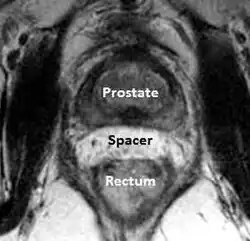

Prostata-Rektum-Hydrogel-Abstandshalter

Bei Prostatakrebs ist eine Strahlentherapie, die entweder in Form einer Brachytherapie oder externen Strahlentherapie durchgeführt wird, eine der am häufigsten gewählten Behandlungsmethoden.

Obwohl die Strahlentherapie bei Prostatakrebserkrankungen im Vergleich zu anderen Behandlungsmethoden bessere Erfolge zeigt, birgt die Verletzung des Rektums durch die Bestrahlung (strahleninduzierte Proktitis) eine Gefahr, da sich das Rektum unmittelbar hinter der Prostata befindet. Die durch Strahlen ausgelöste Schädigung des Rektums kann zu Durchfall, rektalem Druck, zur Schleimhautproduktion und zu Blutungen führen. Bis zum Auftreten dieser Symptome kann es sechs bis zwölf Monate dauern. Die Symptome können jedoch zu jedem Zeitpunkt bis zu 30 Jahren nach der Bestrahlungstherapie auftreten.[101][102]

Eine aufkommende Strategie zur Minderung dieser rektalen Schädigung ist die Platzierung eines Abstandshalters zwischen diesen beiden Strukturen, wodurch das Rektum auf wirkungsvolle Art und Weise vom hochdosierten Strahlenfeld weggedrückt wird. Forschern war es möglich, diese Abstandshalter herzustellen, indem sie verschiedene Materialien in dem potenziellen Raum zwischen der Prostata und dem Rektum platzierten.

Die Injektion von Hyaluronsäure in den Raum zwischen Prostata und Rektum führte zu einem zusätzlichen Raum von mehr als einem Zentimeter ohne Beschwerden durch Tenesmen oder das Gefühl einer rektalen Füllung. Bei Patienten, die mit Hyaluronsäure behandelt wurden, traten im Vergleich zu Patienten, die keinen Abstandshalter aus Hyaluronsäure erhalten hatten, bei proktoskopischen Untersuchungen deutlich seltener rektale Schleimhautbeschädigungen (5 % vs. 36 %, p = 0,002) und keine makroskopischen rektalen Blutungen (0 % vs. 12 %, p = 0,047) auf.[103] Eine ähnliche Studie wurde mittels Collageninjektionen in den gleichen Raum durchgeführt. Mit dieser Methode schuf man einen Raum von durchschnittlich 1,1 cm zwischen der Prostata und dem anterioren Rektum, was zu einer mehr als 50-prozentigen Minderung der rektalen Strahlungsdosis während der Strahlentherapie an der Prostata führte.[104]

Forscher bewerteten einen absorbierbaren Ballon, der in den Raum zwischen Prostata und Rektum eingesetzt wurde, und ermittelten einen beinahe zwei Zentimeter großen Raum mit einer errechneten Reduktion der rektalen Bestrahlung.[105] Untersuchungen von in gleichem Raum injiziertem, absorbierbarem Hydrogel (das sich derzeit in den USA in der Phase der klinischen Erprobung befindet), resultierten in einem zusätzlichen Raum von einem Zentimeter mit einer Minderung der rektalen Strahlung (V70) von 60 %.[106][107]

Obwohl sich die Prostata-Rektum-Abstandshalter noch in der Phase der klinischen Erprobung befinden, besteht ein vielversprechendes Potenzial dahingehend, dass sie nicht nur zur Minderung unbeabsichtigter rektaler Strahlenaussetzung und der daraus resultierenden Komplikationen beitragen, sondern außerdem höhere Dosierungen bei der Strahlentherapie von Krebspatienten ermöglichen. Somit kann die Überlebensrate der Patienten verbessert werden.[108] Zusätzlich kann durch eine höhere Dosierung pro Behandlung eine vollständige Behandlung mit weniger Arztbesuchen realisiert werden, was zum einen angenehmer für den Patienten ist und zum anderen zu erheblichen Einsparungen der medizinischen Kosten führt.[109]

Im Gegensatz zu den USA, in denen sich das Hydrogel noch in der klinischen Erprobung befindet, ist das Hydrogel in Europa bereits CE-zertifiziert und in einigen Ländern auf dem Markt erhältlich.